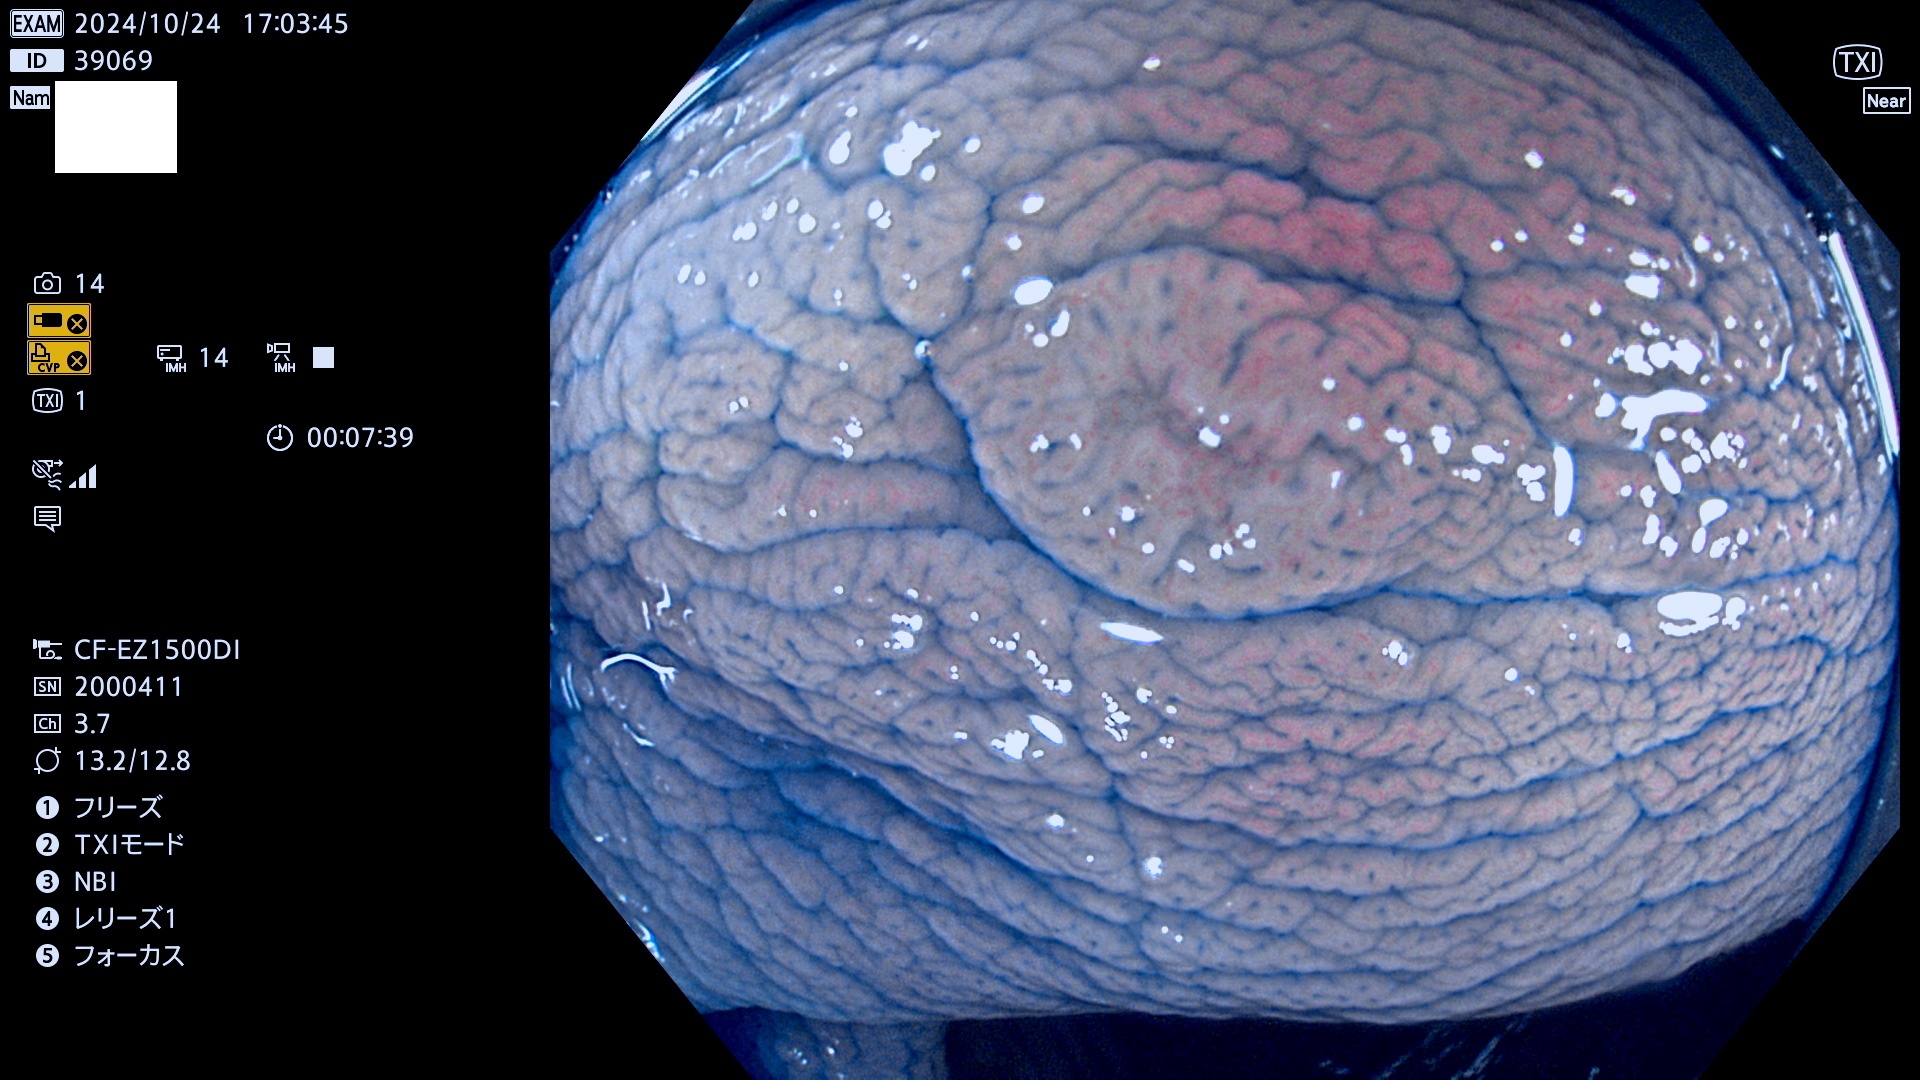

完全に平坦な物をUb、陥凹している物をUcと呼びます。最も発見が難しく危険な病変です。

毎週の検査(木・金・土・日)に発見されたUb、Uc型・腺腫を、その週の日曜の夜にUPし1週間、提示します。

抽出の対象期間 2024年10月24日〜10月27日の4日間(48件の検査)7件 (7/48=15%)